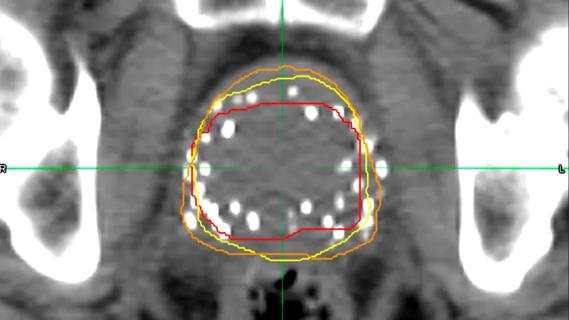

December 2, 2025/Neurosciences/Podcast

Neurological Use of Stereotactic Radiosurgery: Expanding Insights and Indications (Podcast)

An update on the technology from the busiest Gamma Knife center in the Americas